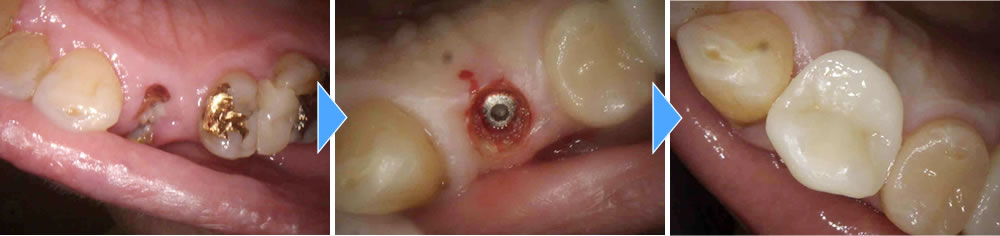

インプラント治療の実施

歯医者がかなり久々とのことで、むし歯により歯が根本から折れてしまった部位や、むし歯が大きく感染をおこしてしまい残すことができない歯を抜歯し、インプラントを埋入しました。

感染により骨が大きく損失してしまっている部位には骨造成を同時に行い、なるべくインプラントの持ちが良くなるようにしました。治療後は今まで噛むことが出来なかった部位でしっかりと噛むことが出来るようになり、大変満足していただいております。